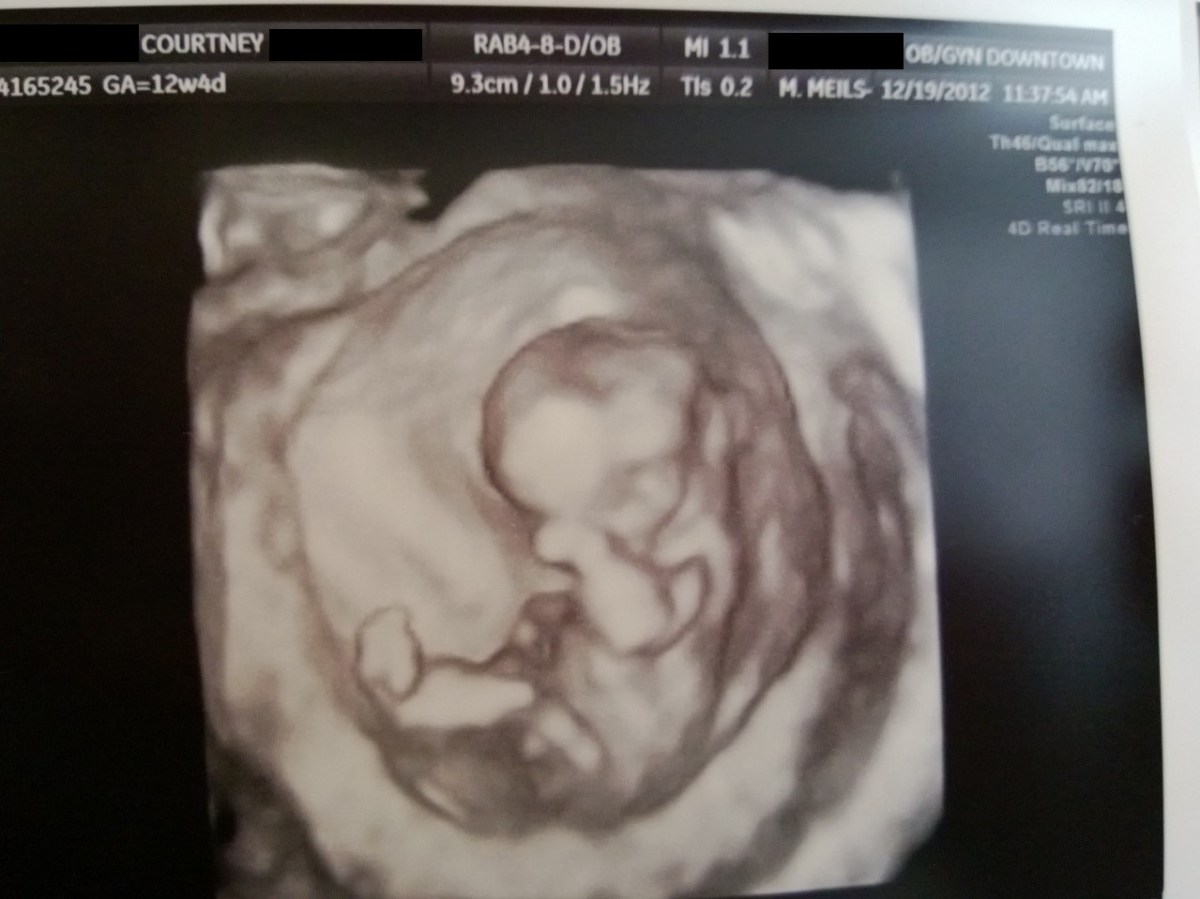

WP_20121219_008 December 27, 2012 by Courtney Leave a comment ← Previous Image Next Image → 12w4d Like Loading...